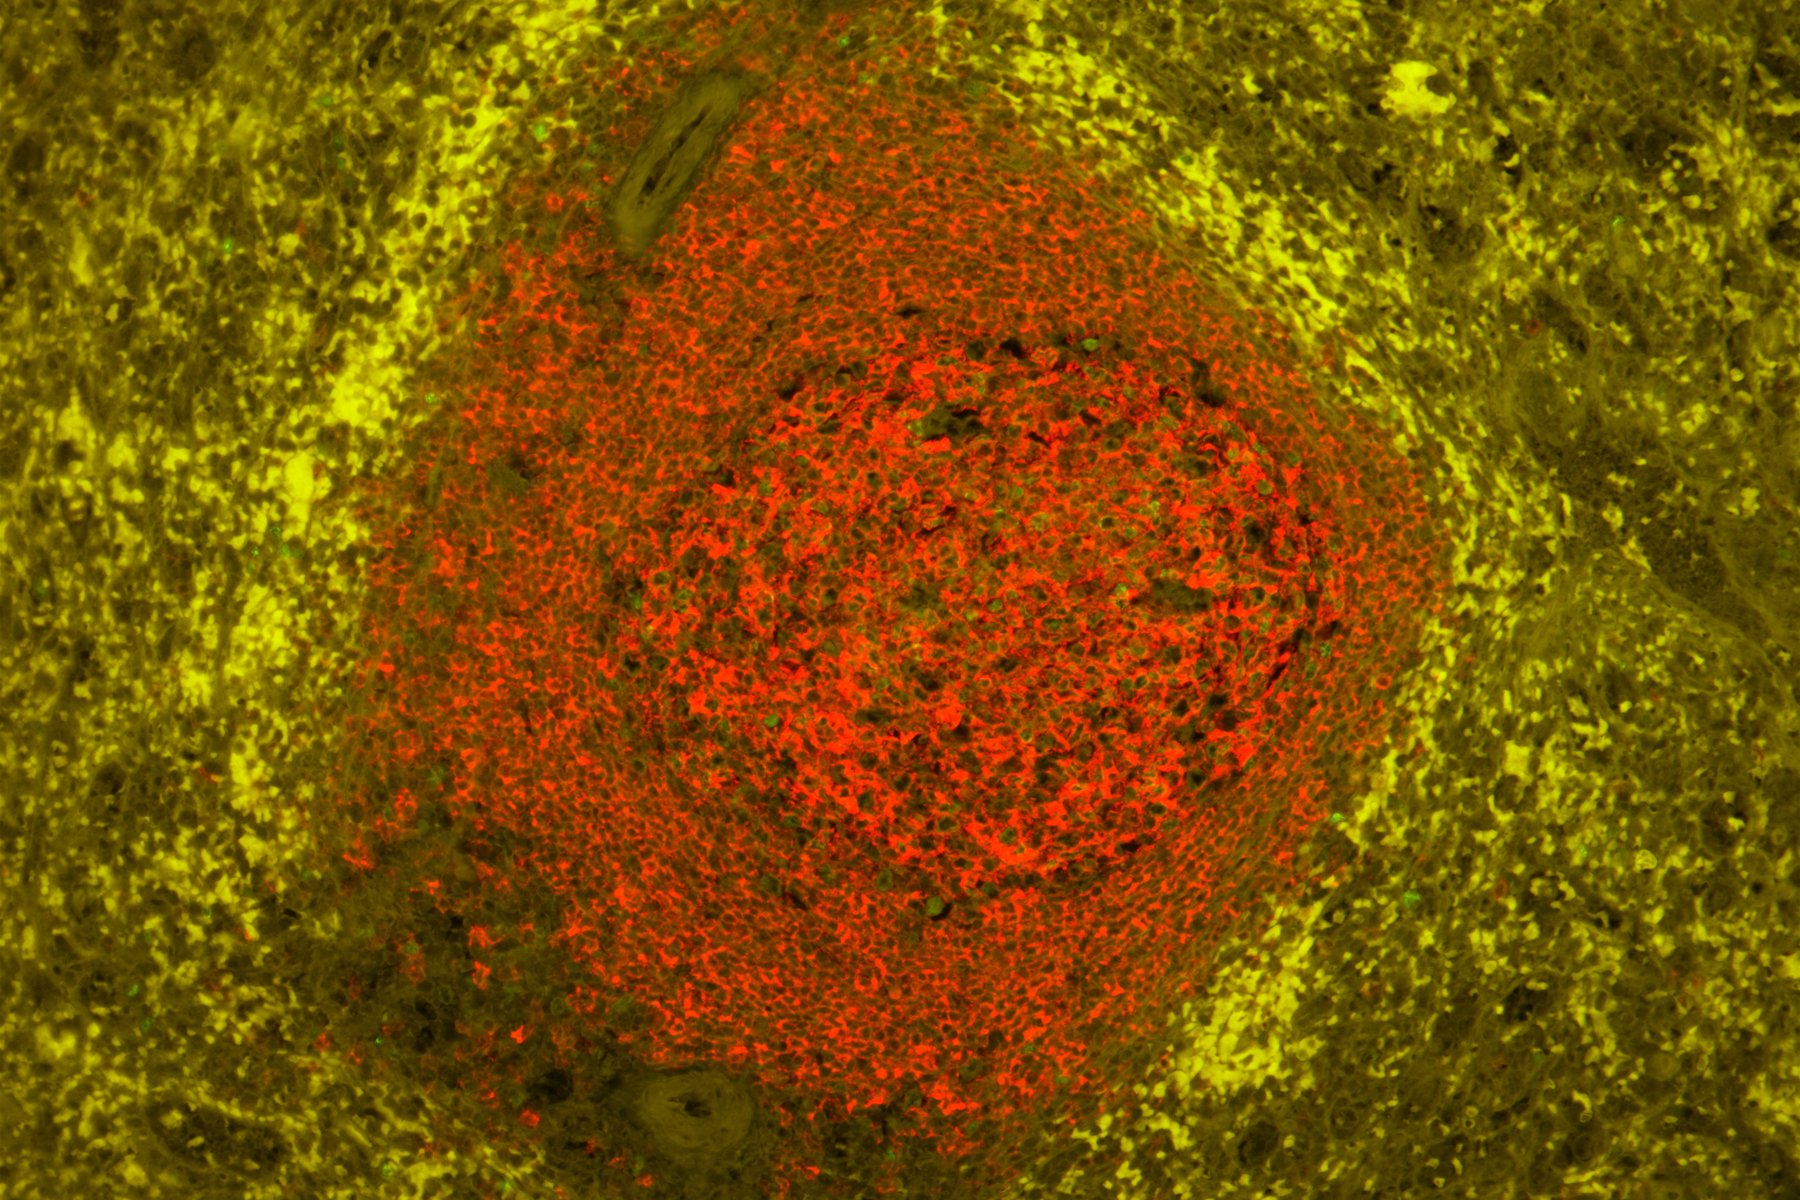

Dva snímky výše: Preparáty z lidské sleziny (FFPE) zabarvené k použití myších anti-CD20 (červená) a králičích anti-Ki67 (zelená) primárních protilátek detekovaných pomocí sady VectaFluor Duet kit (DK-8818). Povšimněte si významného potlačení autofluorescence na ošetřeném řezu (nahoře) při zachování dobře ohraničeného specifického signálu jak červeného, tak zeleného kanálu.